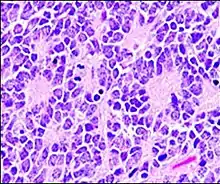

Micrograph of an ameloblastoma showing characteristic palisading. H&E stain.

Palisades that are generally longer than a rosette or pseudorosette can be seen in neural tumors such as Schwannoma,[16][17] as well as in ameloblastomas. It can also be seen in nodular basal-cell carcinomas.[18]